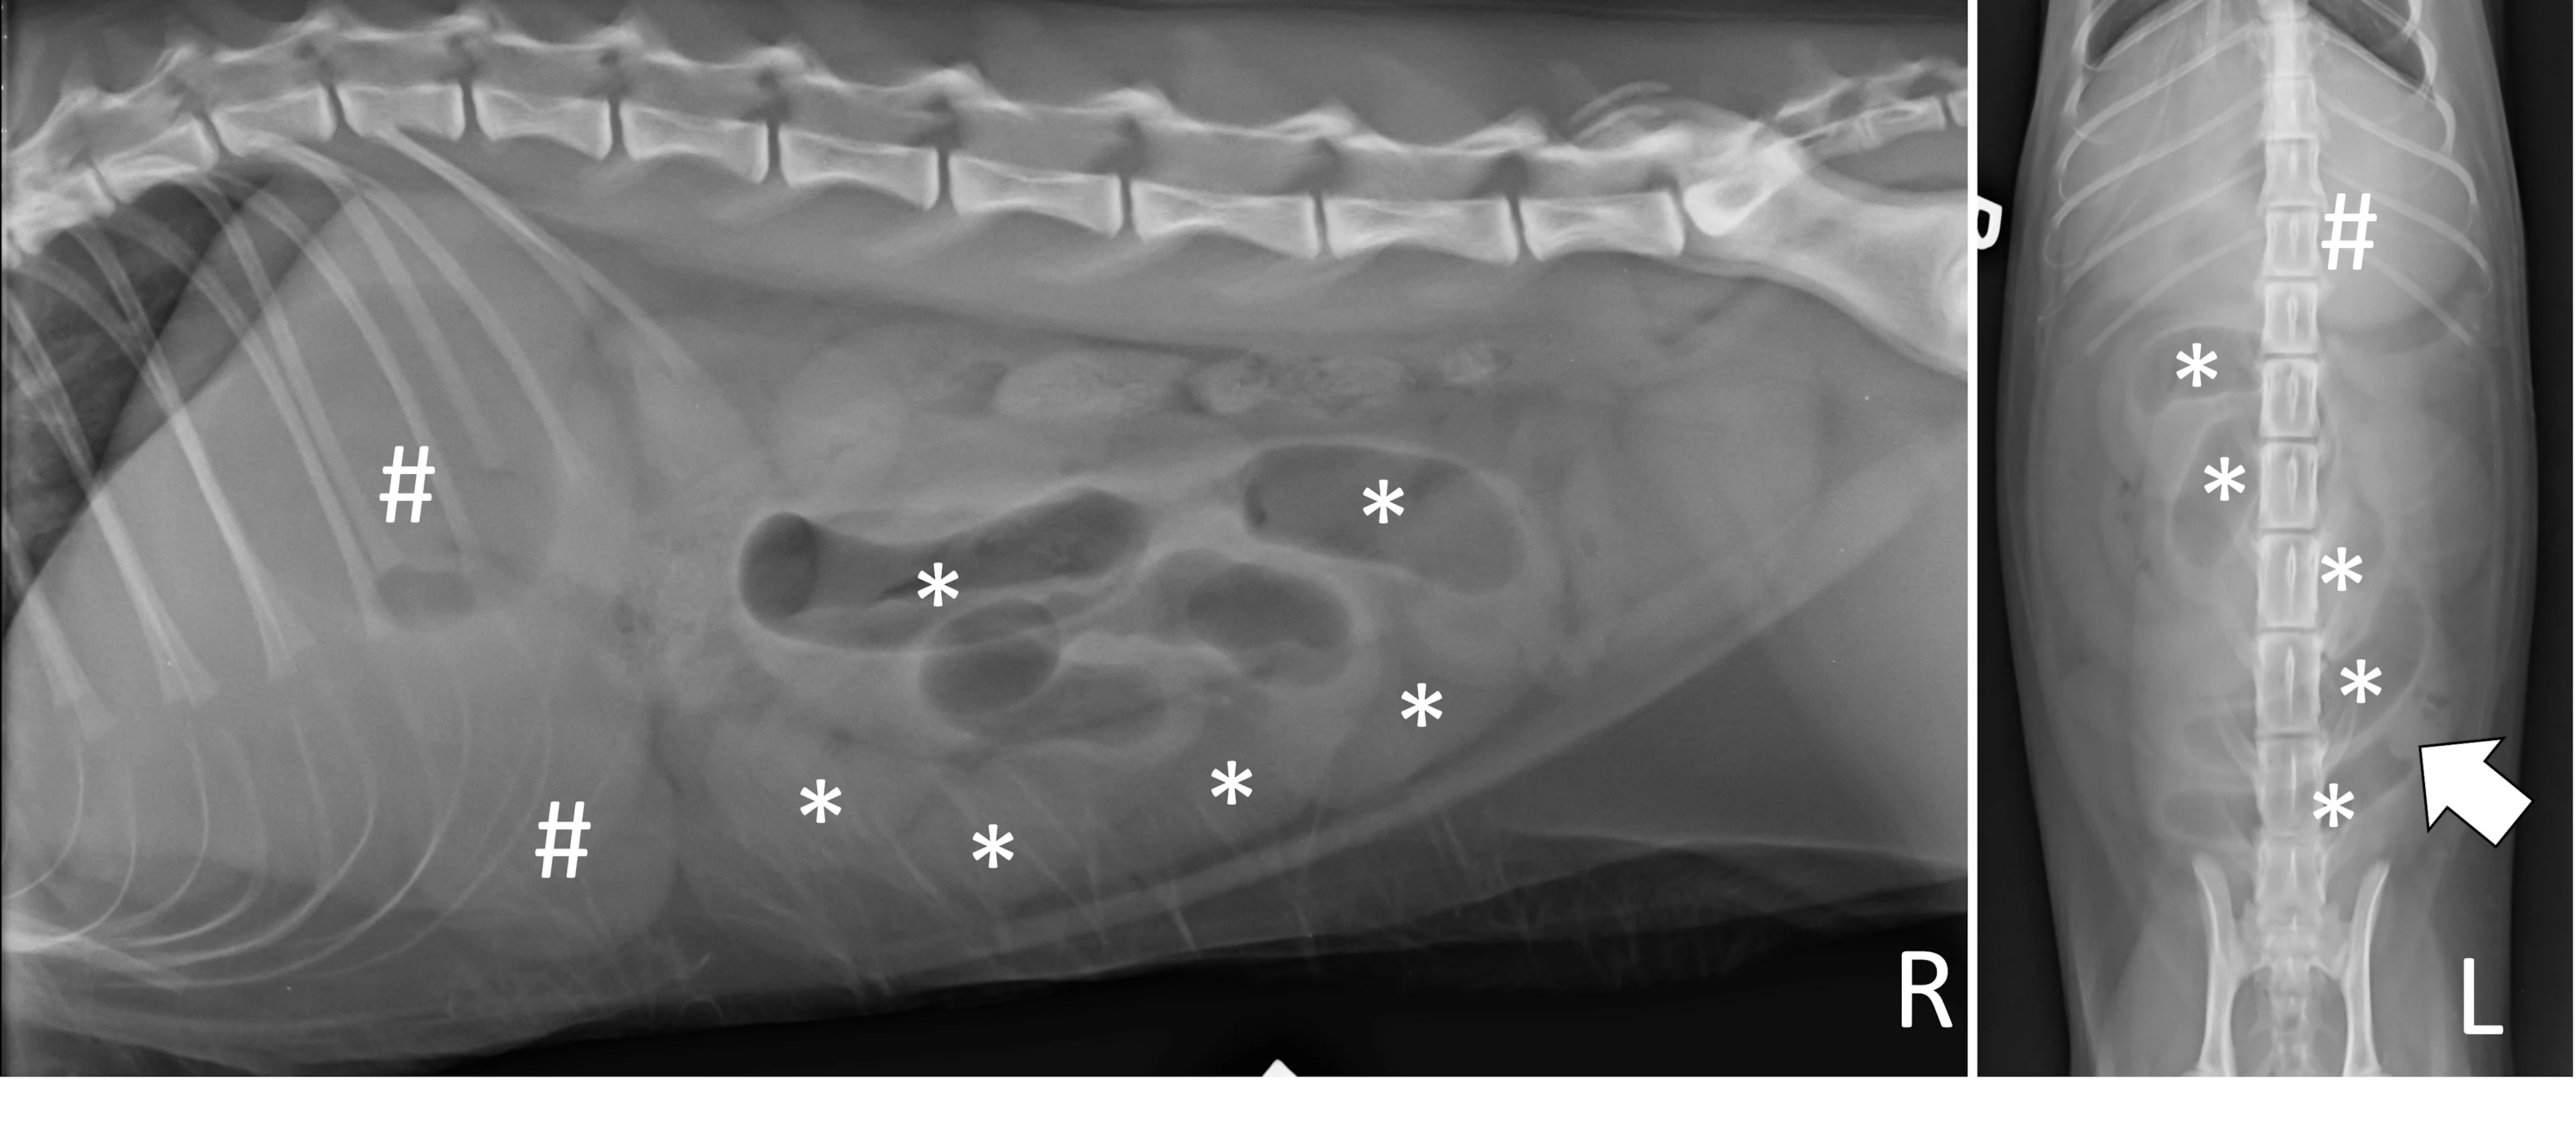

Small Intestinal Mechanical Obstructions

Small intestinal mechanical obstructions occur when a foreign body blocks the lumen of any segment of the small bowel, causing segmental dilation located orad to the foreign body. As the small bowel increases in size, it becomes crowded in the peritoneal space and begins stacking on itself with sharp, hairpin turns (Figure 4).1 Dilated portions of the small bowel usually contain a mixture of fluid and gas. Occasionally, intraluminal gas may outline part of a foreign body, making the object easier to see. Although the diameter of the small intestine can be objectively measured and compared with the height of the center of the L5 vertebral body,6,7 one study found that using the small intestinal diameter:vertebral body height ratio did not increase the diagnostic accuracy for mechanical obstruction on radiographs regardless of clinician experience.8

Right lateral and ventrodorsal abdominal radiographs of a 1-year-old neutered male domestic shorthair cat with a small intestinal mechanical obstruction from a surgically confirmed earplug lodged in the distal jejunum. The stomach is mildly dilated with fluid and gas (pound signs). Segmental fluid and gas dilation of the small bowel with stacking and hairpin turns can be seen (asterisks). On the ventrodorsal projection, intraluminal gas outlines the margin of the earplug (arrow).